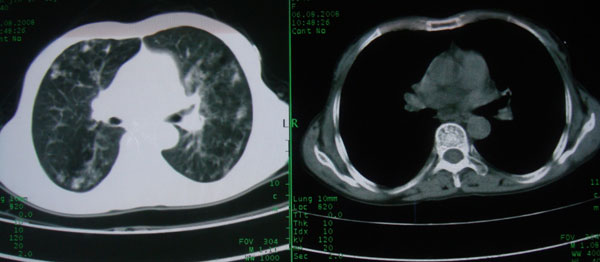

多考虑支气管扩张并感染,双下肺继发性肺结核不除外

周围型肺癌征象不明显,应不予首先考虑

考虑支气管肺泡癌可能性大

慢性支气管炎伴支气管扩张、感染,间质纤维化。

慢性支气管炎伴全小叶型肺气肿、支气管扩张、感染、间质纤维化